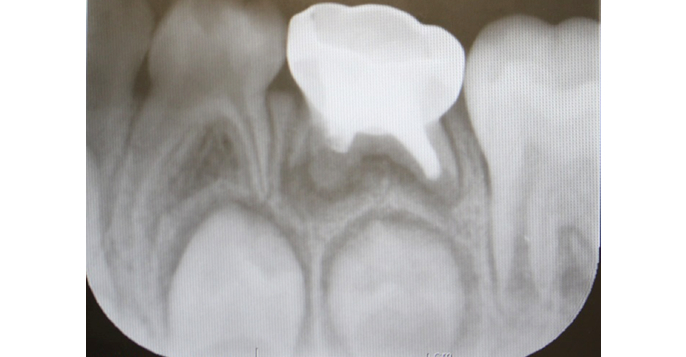

- 来院の理由

- 穴が大きくなってきたので、近くの歯医者さんで治療したが、手足が動いてしまい、治療ができなかったので治療して欲しい。

- 治療期間

- 1か月

- 治療内容について

- 仮の蓋をしてもらっている状態で来院されました。 治療前のレントゲン写真より、神経のお部屋近くまで虫歯が進行しているのがわかります。 レントゲン写真では、見た目よりも虫歯が深く進行しているのがわかります。 残念ながら、虫歯は深く、神経の処置を行いました。 乳歯の下で永久歯が育ち始めている時期です。乳歯の治療をしないと、永久歯の成長を阻害することもあります。